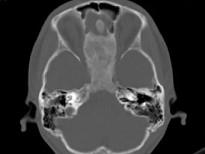

问题 女,17岁,鼻阻塞、头痛两年.如图所示符合筛骨病变最可能的诊断是 ( )

选项 A、骨瘤 B、骨化性纤维瘤 C、纤维异常增殖症 D、软骨瘤 E、成骨肉瘤

答案 B